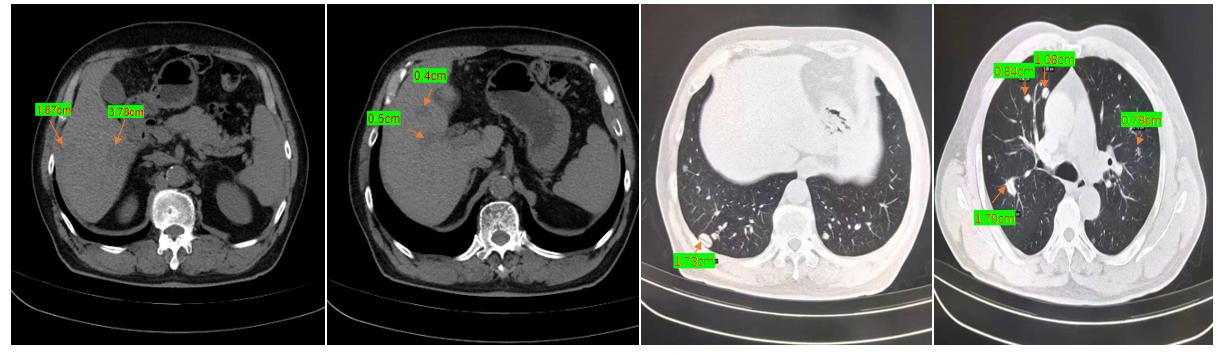

复查CT显示:双肺、肝脏多发转移灶较前增大(图1),肿瘤标志物CEA骤升至383 ng/ml(后最高达524 ng/ml),病情急剧恶化。

复查CT提示:肺部靶病灶由1.73cm缩小至 0.94cm(下降46%),肝部病灶由1.87cm缩小至 1.03cm(下降45%)。CEA降至 24.1 ng/ml(较峰值下降95%以上)。